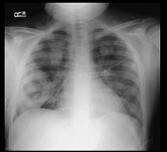

问题 男,35岁,发热,贫血,血尿,既往有副鼻窦炎,结合X线图像,最可能的诊断是 ( )

选项 A.肺脓肿 B.周围型肺癌 C.肺转移瘤 D.肺结核 E.韦格肉芽肿

答案 E